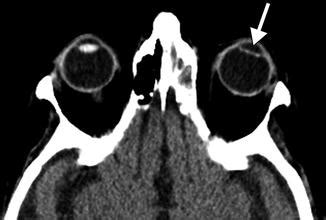

So, what exactly is pseudophakia ? The term itself breaks down like this: “pseudo” means false or artificial, and “phakia” refers to the presence of a lens in the eye. Put them together, and you’ve got pseudophakia : the state of having an artificial lens. This artificial lens, known as an intraocular lens (IOL), is implanted in the eye to replace the natural lens that has become cloudy due to cataracts. Cataracts, by the way, are a common age-related condition where the natural lens of the eye becomes opaque, leading to blurred vision. Think of it like looking through a foggy window – that’s what cataracts do to your vision. Pseudophakia is the solution to restore clear vision once the natural lens is no longer doing its job.